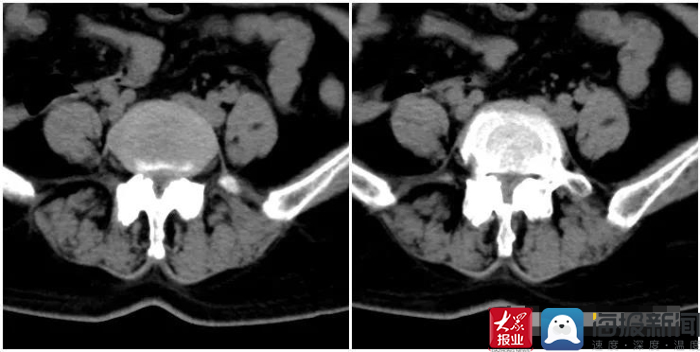

*安泰**市中医医院脊柱外科医师王乃舜对患者详细查体并完善相关检查后,发现患者多节段椎间盘突出,以腰4、5椎间盘为重,并相应黄韧带肥厚,腰4椎体滑脱,腰椎管严重狭窄,遂建议患者住院手术治疗。